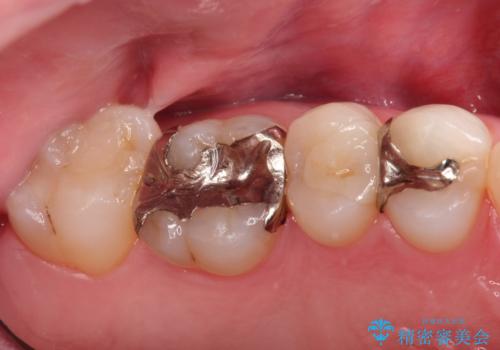

- 金属のインレーを除去を希望されて来院されました。

セラミックインレーにて治療を行なっております。

e-max プレスインレーにて修復治療を行っているため適合性及び審美性の高い治療を行うことができます